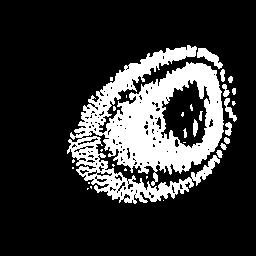

To better retain the deep features of an image and solve the sparsity problem of the end-to-end segmentation model, we propose a new deep convolutional network model for medical image pixel segmentation, called MC-Net. The core of this network model consists of four parts, namely, an encoder network, a multiple max-pooling integration module, a cross multiscale deconvolution decoder network and a pixel-level classification layer. In the network structure of the encoder, we use multiscale convolution instead of the traditional single-channel convolution. The multiple max-pooling integration module first integrates the output features of each submodule of the encoder network and reduces the number of parameters by convolution using a kernel size of 1. At the same time, each max-pooling layer (the pooling size of each layer is different) is spliced after each convolution to achieve the translation invariance of the feature maps of each submodule. We use the output feature maps from the multiple max-pooling integration module as the input of the decoder network; the multiscale convolution of each submodule in the decoder network is cross-fused with the feature maps generated by the corresponding multiscale convolution in the encoder network. Using the above feature map processing methods solves the sparsity problem after the max-pooling layer-generating matrix and enhances the robustness of the classification. We compare our proposed model with the well-known Fully Convolutional Networks for Semantic Segmentation (FCNs), DecovNet, PSPNet, U-net, SgeNet and other state-of-the-art segmentation networks such as HyperDenseNet, MS-Dual, Espnetv2, Denseaspp using one binary Kaggle 2018 data science bowl dataset and two multiclass dataset and obtain encouraging experimental results.